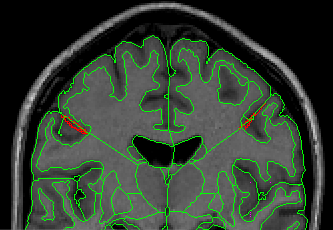

Step Four: When the Central Sulci lines drawn in the axial view appear in the coronal view (as “dots”) (Fig 15), connect the exterior at this sulcus with the white matter medial to it with a straight line (Fig 16). Extract the cortex superior to this and label it as Frontal Lobe (Fig 17).

Figure 15

Figure 16

Figure 17